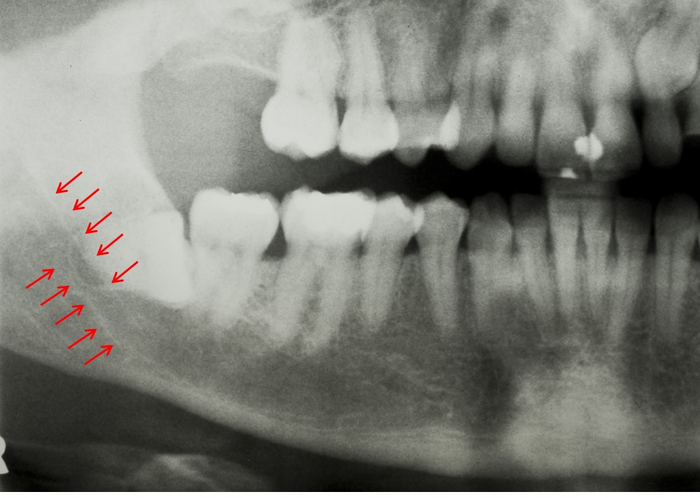

아래 사진에서 빨간 화살표로 표시한 흰 줄이 두 개 보이시죠?

아래턱을 지나가는 터널 같은 구조입니다.

이것을 하악관(Mandibular canal)이라고 합니다.

하악관은 계란껍질 만한 두께를 가진 벽으로 둘러 쌓여 있습니다.

이 하악관으로 입술, 아래턱의 피부, 잇몸의 감각을 담당하는 신경(하치조신경, Inferior alveolar nerve)이 지나갑니다.

그리고 치아와 아래턱에 혈액을 공급하는 큰 혈관도 지나가죠.